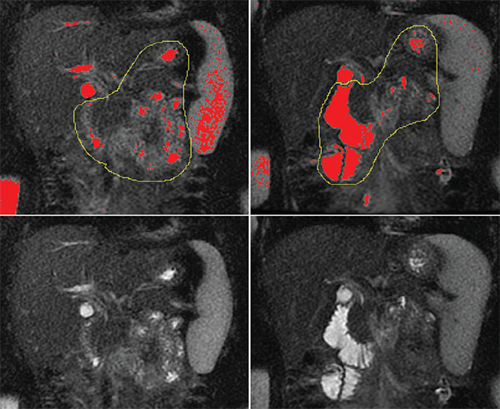

In recent years, radiologists and gastroenterologists have been working to use magnetic resonance imaging (MRI) as a non-invasive alternative. MRI allows the fluid secreted into the intestine to be visualized and measured without placement of any tube. Until now, no reference set of normal data had been assembled for children.

Their team recruited 50 healthy children, ages 6 to 16, to define normal pancreatic secreted fluid volumes and secretion rates, as measured by MRI, in response to secretin. Images were obtained before secretin administration and at one, five, 10 and 15 minutes afterward.